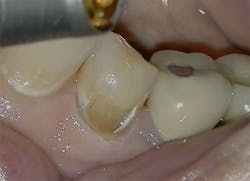

Figure 4: Class V pre-op lesion. Photo courtesy of Jeff Rhode, DDS.

For the same reasons, the 10.6-micron CO2 laser has also been shown to damage the implant surface and increase the temperature of the adjacent hard and soft tissue surrounding the dental implant.4 Because of the difference in wavelength, absorption pattern, and introduction of water irrigation with the 9.3-micron CO2 laser (figure 1), it can now be used for hard-tissue applications. This laser has been used to prepare teeth for Class I–IV (figures 2–8) restorations without the concern of raising pulpal temperature and inducing necrosis. The laser has also been used as an alternative to conventional high-speed drills to prepare teeth for crowns, bridges, and veneers.